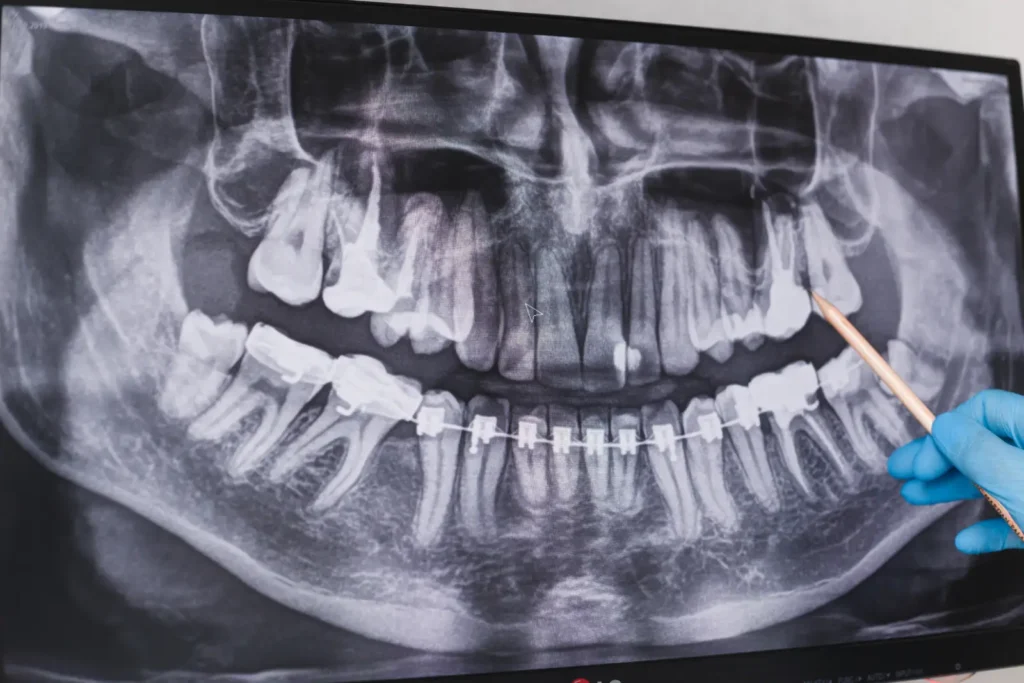

When there is not enough room in the jaw for wisdom teeth to come through properly, they can become trapped under the gum or only partially erupt. Treatment by a qualified dental professional can prevent damage to the neighbouring teeth and supporting bone. Impacted wisdom teeth are common because there is often not enough space in the jaw for them to emerge correctly.

Because of these problems, many oral surgeons and dentists in Brisbane recommend removing troublesome third molars to help keep the gums, jawbone and teeth healthy in the long term.